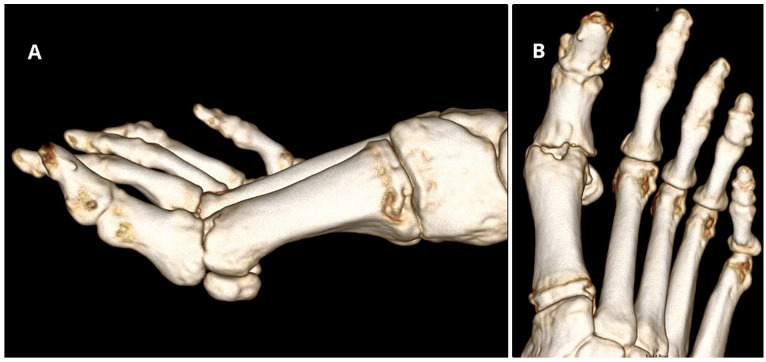

Methods: We report the case of a 43-year-old woman with persistent pain and functional limitations after a failed PVA hydrogel implant in the first MTP joint. The revision surgery involved a biologic resurfacing using the Osteochondral Autograft Transfer System (OATS) with a graft harvested from the ipsilateral femoral condyle, complemented by interpositional arthroplasty with a dermal graft and a proximal phalanx closing wedge osteotomy to correct residual hallux valgus.

Results: At the 3-year follow-up, the patient-reported complete resolution of pain and returned to full activity with improved range of motion (40 degrees dorsiflexion, 15 degrees plantarflexion). Radiographic evaluation demonstrated graft incorporation and restoration of joint space, confirming the success of the procedure.